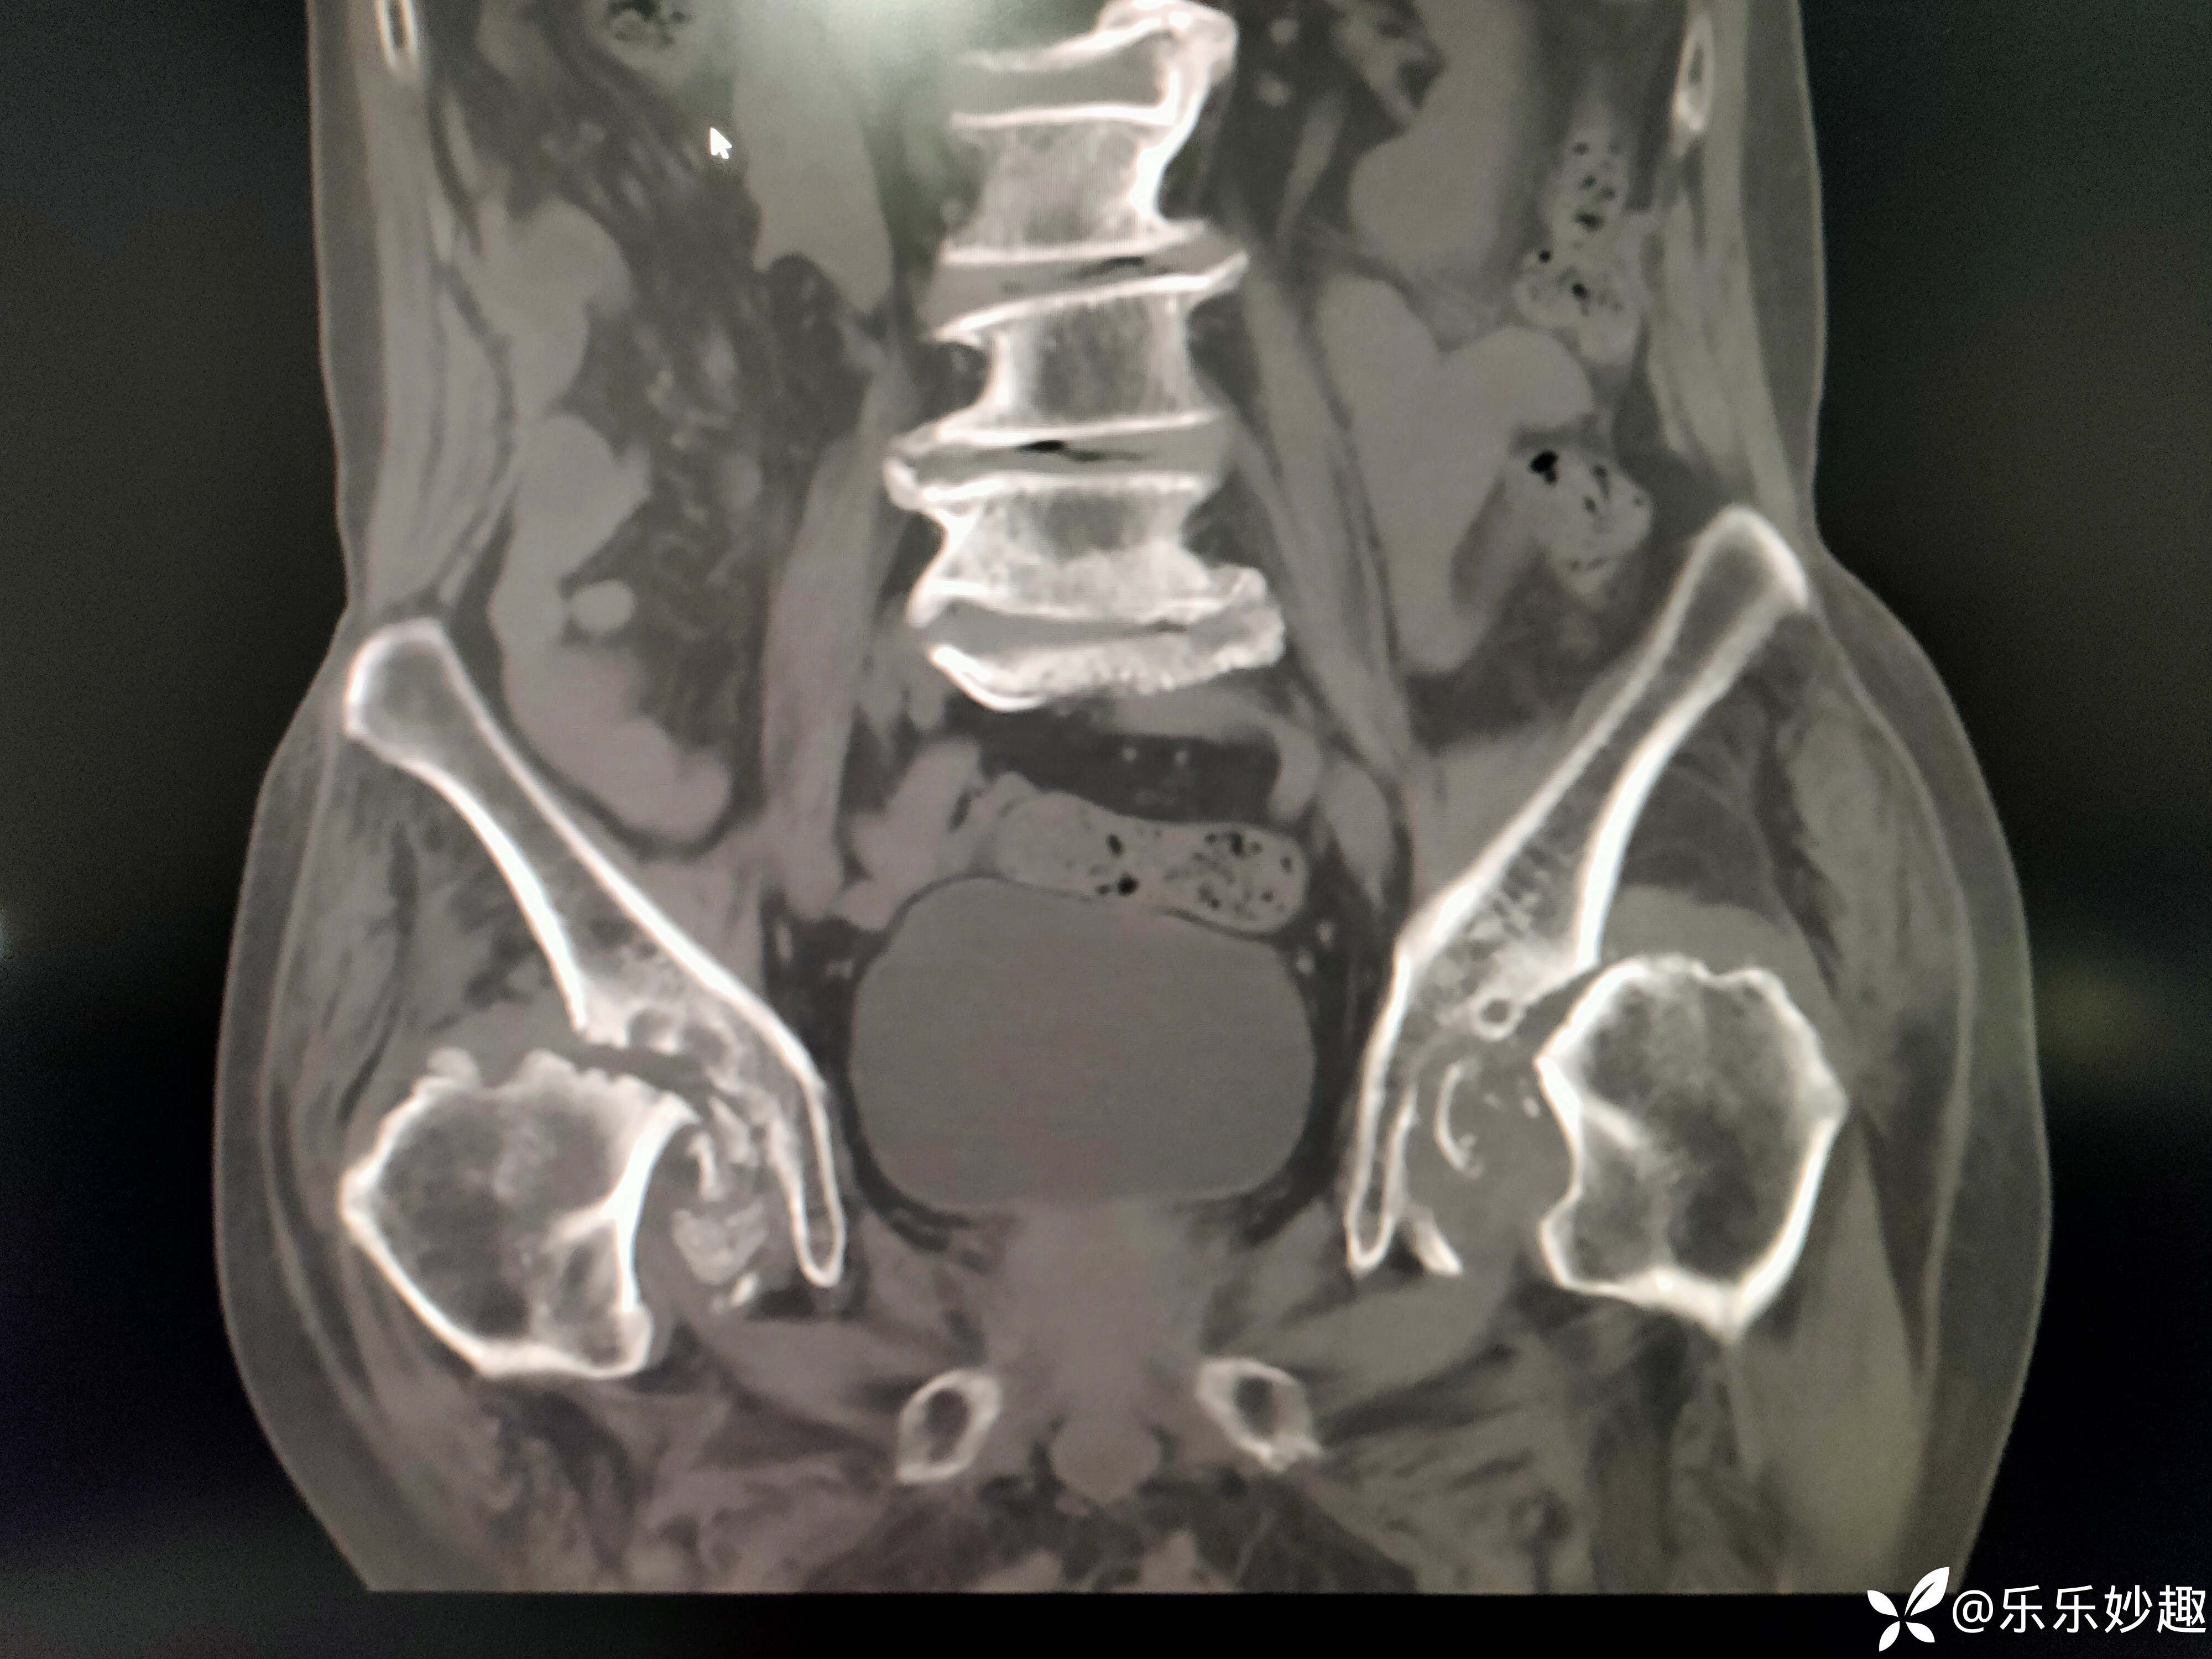

然后做了CT,见下图